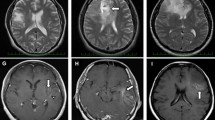

MTR asym at 3.0 ppm was significantly lower in 1p/19q co-deleted gliomas

MTRasym at 3.0 ppm within tumor ROI were significantly lower in 1p/19q co-deleted gliomas compared to 1p/19q non-co-deleted ones (co-deleted, 1.17% ± 0.32%; non-co-deleted, 1.72% ± 0.41%, P = 1.13 × 10−7, Fig. 2a). The significant difference in MTRasym persisted when comparing within grade II (co-deleted, 1.12% ± 0.29%; non-co-deleted, 1.62% ± 0.35%, P = 4.17 × 10−5, Fig. 2b) and grade III (co-deleted: 1.29% ± 0.35%; non-co-deleted: 1.80% ± 0.44%; P = 4.21 × 10−3, Fig. 2c). Within gliomas exhibiting classical oligodendroglial histological features (including oligodendroglioma, oligoastrocytoma, anaplastic oligodendroglioma, and anaplastic oligoastrocytoma), the MTRasym remained significantly lower in 1p/19q co-deleted tumors compared to non-co-deleted ones (co-deleted, 1.17% ± 0.32%; non-co-deleted, 1.71% ± 0.42%, P = 5.16 × 10−5, Fig. 2d). When comparing within the IDH mutant gliomas, the same significant difference remained (co-deleted, 1.17% ± 0.32%; non-co-deleted, 1.66% ± 0.34%, P = 8.72 × 10−7, Fig. 2e).

Comparison of MTRasym between 1p/19q co-deleted and non-co-deleted gliomas in T2 hyperintense lesions. (a–e) Show the comparison within all patients, WHO grade II gliomas, grade III gliomas, gliomas with oligodendroglial component, and IDH mutant gliomas, respectively. Each patient data point is represented by a dot and the violin plots represent the distribution of the patient data. In all patient cohorts, significantly lower MTRasym is observed in 1p/19q co-deleted gliomas compared to 1p/19q non-co-deleted gliomas (**, P < 0.01; ***, P < 0.001; ****, and P < 0.0001). The ROC analyses for differentiating 1p/19q co-deletion status in patients with WHO grade II and/or III gliomas using MTRasym are demonstrated in (f). The colored dots represent the optimal operating points.

The ROC analysis (Fig. 2f) showed that the prediction of 1p/19q status in WHO grade II and III gliomas using MTRasym with a threshold of 1.55% had sensitivity of 70.7%, specificity of 92.9%, accuracy of 79.7%, and AUC of 0.85. The performance of classifying 1p/19q status within either grade II or grade III gliomas was similar, with AUC of 0.86 for grade II (threshold, 1.46%; sensitivity, 72.2%; specificity, 89.5%; and accuracy, 81.1%) and AUC of 0.82 for grade III (threshold, 1.65%; sensitivity, 69.6%; specificity, 88.9%; accuracy, 75.0%). The classification within tumors exhibiting oligodendroglial histological features (AUC = 0.86) and within IDH mutant gliomas (AUC = 0.85) showed similar performance (ROC curves not shown).

MTR asym characteristics across grades and IDH mutation status

We further performed comparison of median MTRasym at 3.0 ppm within tumor ROI between grade II and grade III gliomas. We found significantly higher MTRasym in grade III gliomas (grade II, 1.34% ± 0.40%; grade III, 1.68% ± 0.46%, P = 1.16 × 10−3, Fig. 3a). Within 1p/19q non-co-deleted gliomas, the difference in MTRasym between grade II and III was not significant (grade II, 1.62% ± 0.35%; grade III, 1.80% ± 0.44%, P = 0.16, Fig. 3b). Also, there was no significant difference between grade II and III within 1p/19q co-deleted gliomas (grade II, 1.12% ± 0.29%; grade III, 1.29% ± 0.35%, P = 0.18, Fig. 3c). Regarding the IDH mutation status, MTRasym in IDH mutant gliomas was significantly lower than IDH wild-type gliomas (IDH mutant, 1.41% ± 0.41%; IDH wild-type, 1.83% ± 0.48%, P = 7.17 × 10−4, Fig. 3d), consistent with a previous report18.

Comparison of median MTRasym between grades and between IDH mutant and IDH wild-type gliomas. Grade III gliomas shows significantly higher MTRasym compared to grade II gliomas (a). However, when comparing within 1p/19q non-co-deleted gliomas (b) or co-deleted gliomas (c), the difference is not significant. MTRasym is also significantly higher in IDH wild-type gliomas compared to mutant gliomas (d).